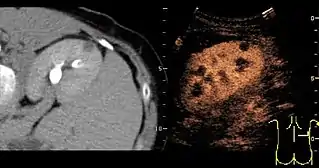

Solid malignant tumors in the kidney do not exhibit specific enhancement patterns like some liver lesions, and no valid enhancement criteria between benign and malignant renal lesions have been proposed. However, CEUS is used in some patients after ablation of renal cell carcinoma to evaluate contrast uptake in the treated area (Figure 30).

Image fusion of ultrasound with a previously recorded dataset of CT or other modalities is rarely used in renal US. Reports on image fusion using CEUS or US combined with CT or MRI in the examination of renal lesions and in difficult US-guided renal interventions have been published (Figure 31). However, no recommendations have been published so far.[1]

Figure 31. Unspecific cortical lesion on CT is confirmed cystic and benign with contrast-enhanced ultrasound (CEUS) using image fusion.[1]